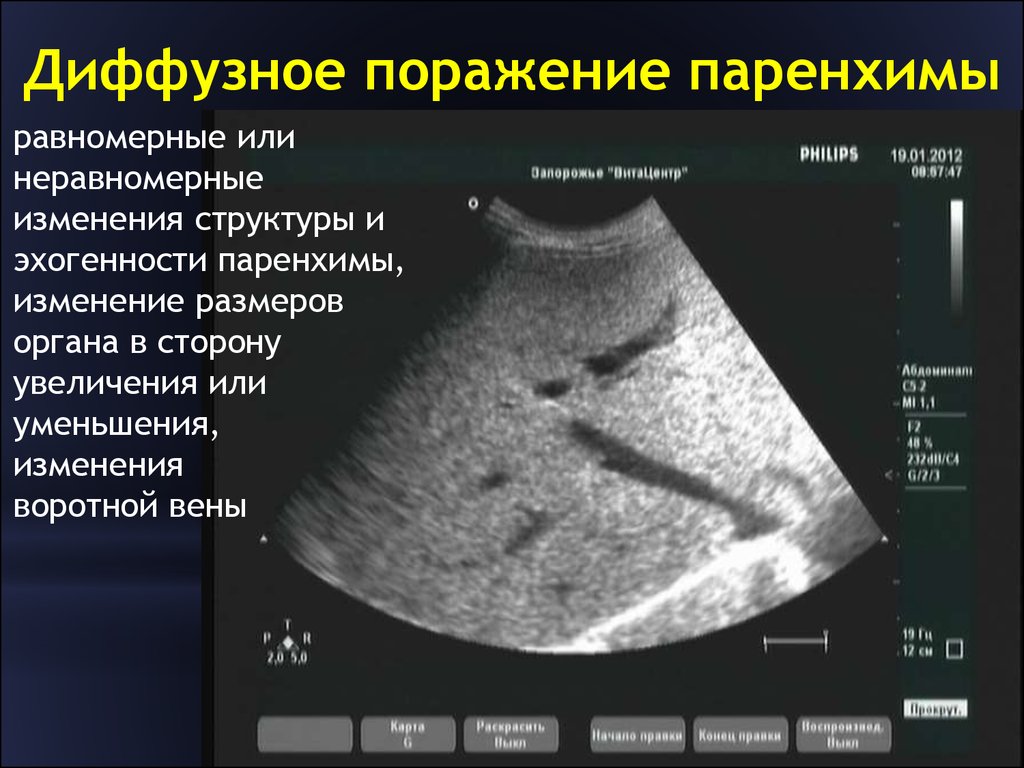

Метастатические поражения печени в ультразвуковом изображении характеризуются